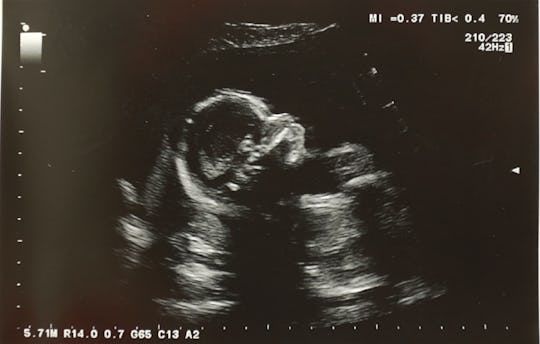

Baby's face looks flat ultrasound. Mine is squished too. If this is how baby is positioned during an ultrasound the the sound waves might reveal only two-thirds or half of babys face. This allows the expecting parents to see their babys face rather than just the outline of the face.

This is particularly clear when. 3D4D ultrasounds differentiate from the 2D ultrasound through the type of images they show. Most people are familiar with traditional 2D ultrasounds which produce black and white flat images that appear grainy and blurred.

This could happen in the womb but. It can look a little odd. Ultrasounds dont pick up fat or cartilage distorting the picture you see.

The only thing was I just have to come back because baby was facing my back so they said it was hard for them to see. A kid might suffer small injuries to the nasal skeleton. However unlike the flat image given by a 2D ultrasound a 3D ultrasound creates the appearance of a three-dimensional image of the baby.

The facial anomalies in Binder syndrome may be isolated. I had my anatomy scan on Wednesday Im 20 weeks. This is because a 2D ultrasounds see through the baby to its internal organs and tissues whereas a 3D or 4D ultrasound will show the babys skin creating a more realistic shape and form to the images.

However many details of facial anatomy can be identified as early as 11 weeks particularly by using transvaginal sonography. The white on the side of the babys face is actually my uterus. Your babys face appears like its smooshed up against your tummy because it really kind of is.